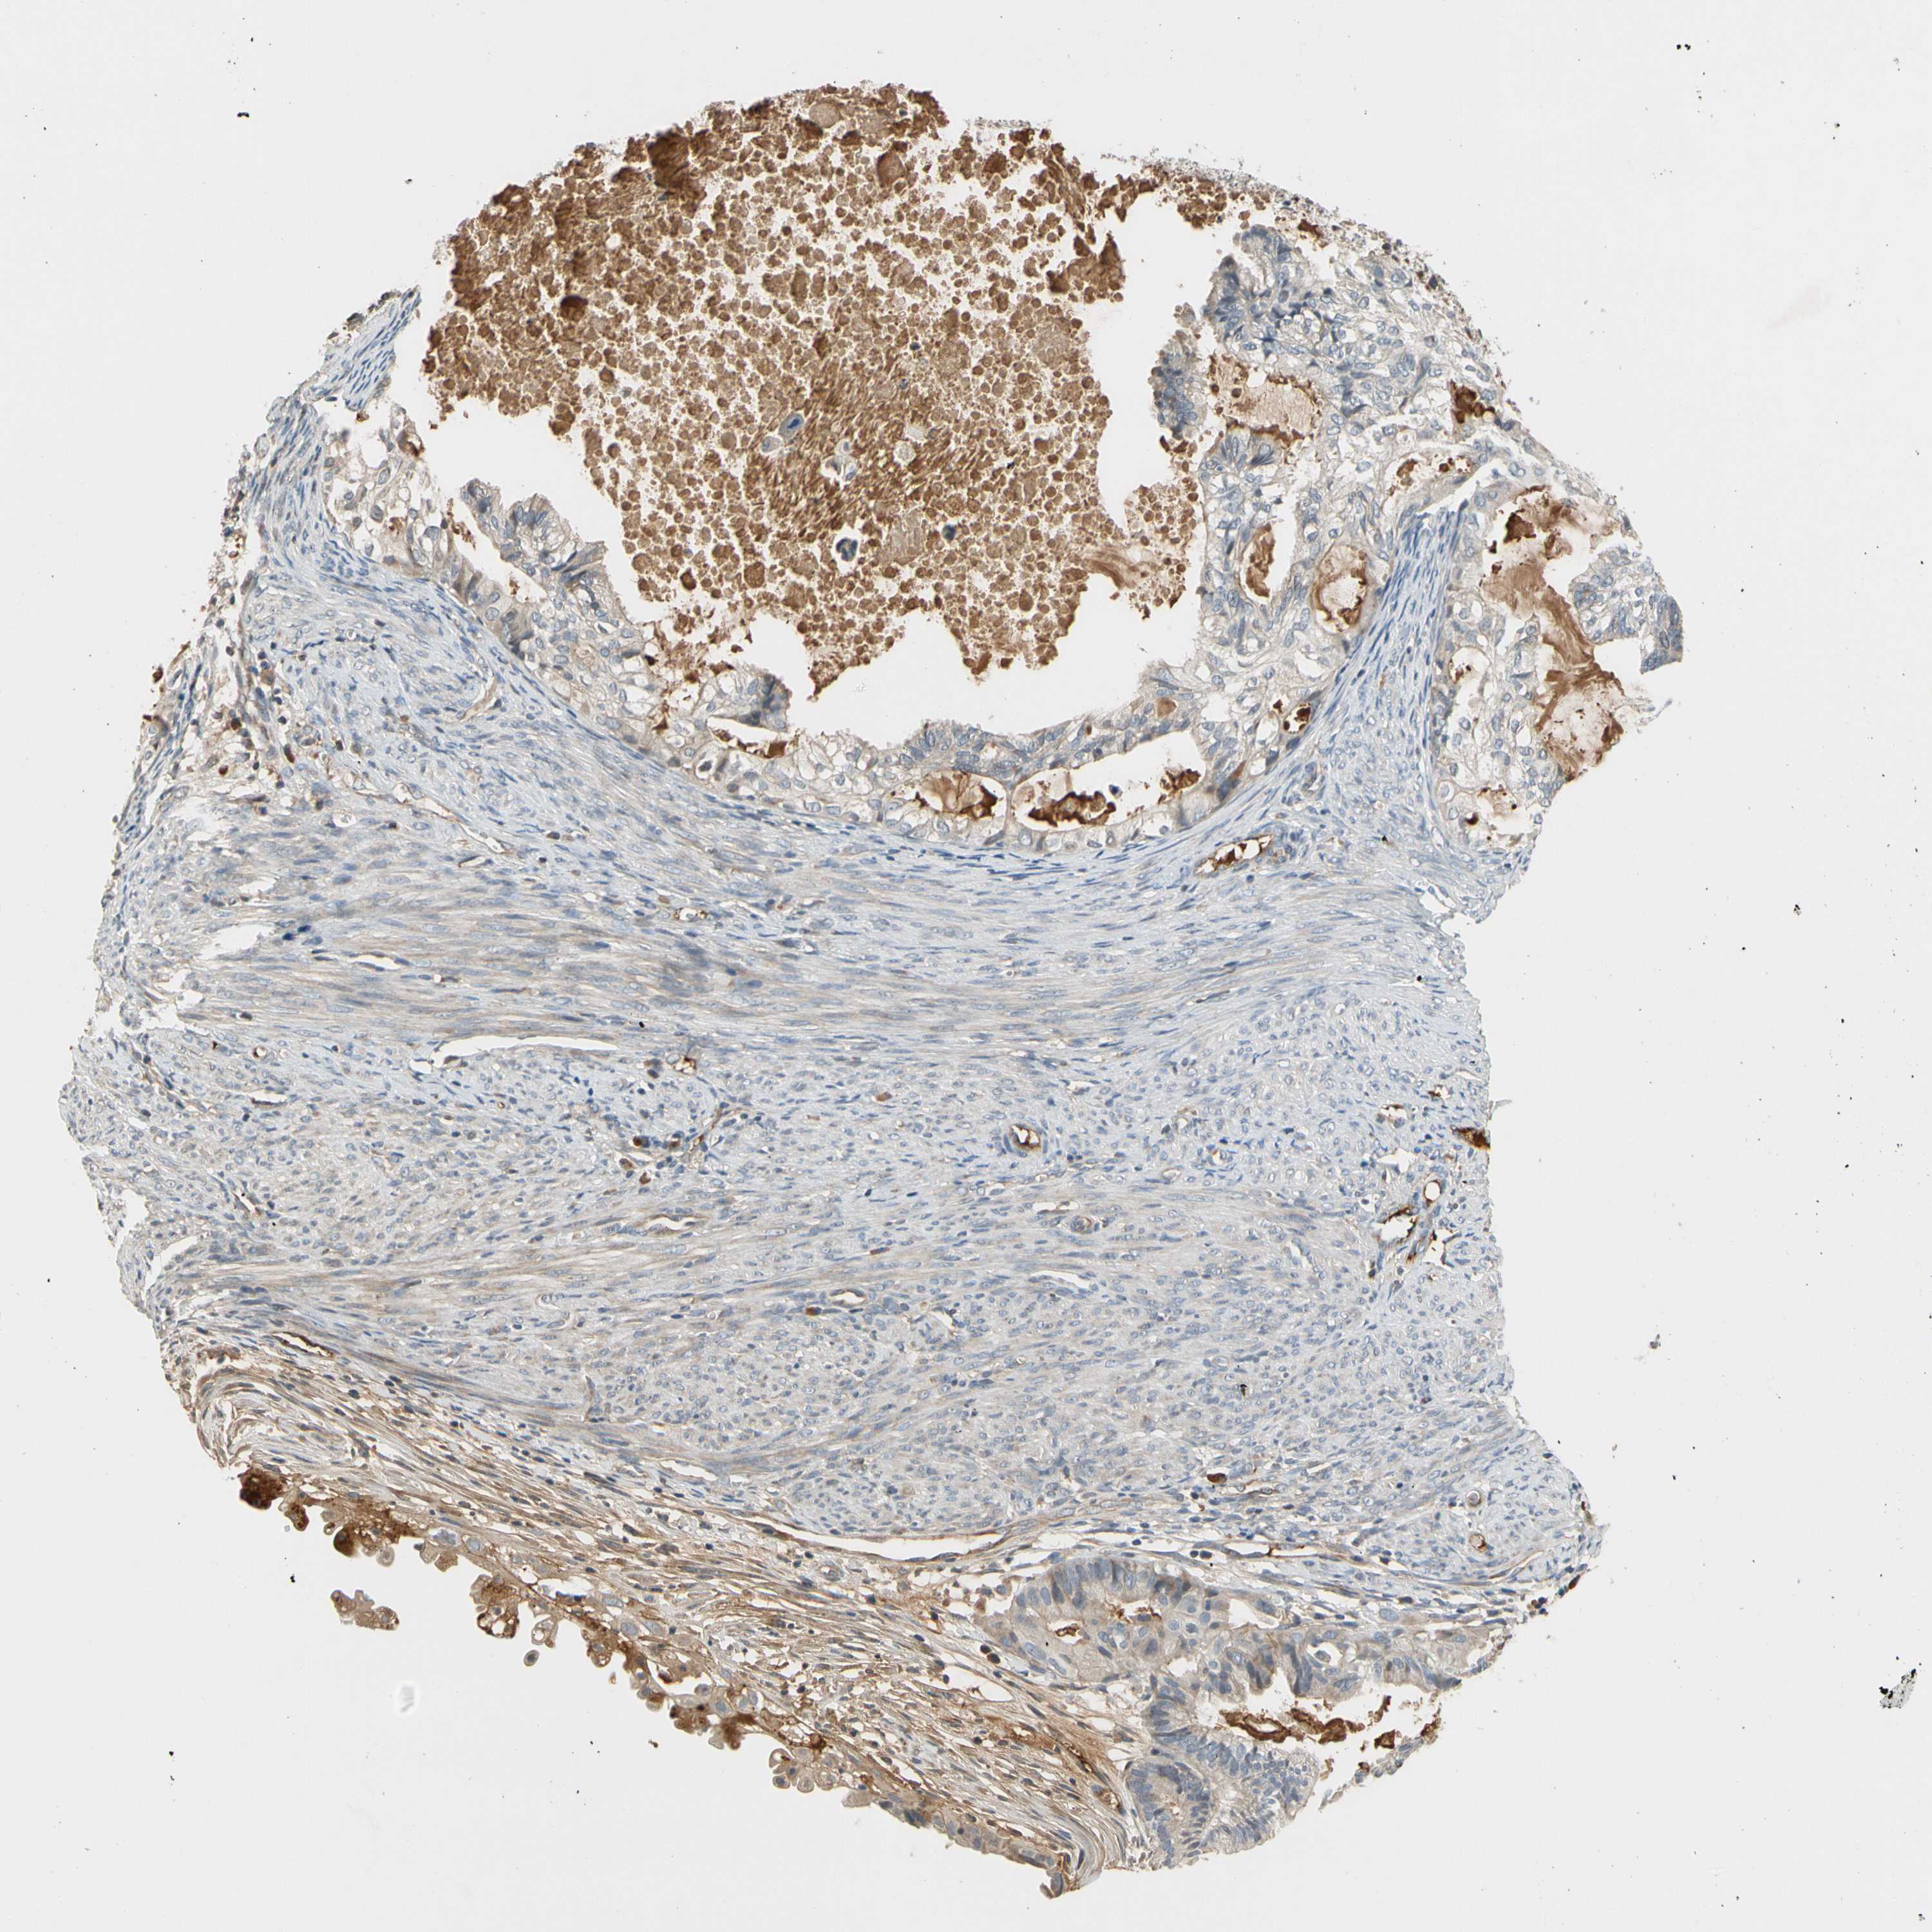

CERVICAL CANCER - Protein expressioni

A mouse-over function shows sample information and annotation data. Click on an image to view it in a full screen mode. Samples can be filtered based on level of antibody staining by selecting one or several of the following categories: high, medium, low and not detected. The assay and annotation is described here.

Note that samples used for immunohistochemistry by the Human Protein Atlas do not correspond to samples in the TCGA dataset.

Antibody stainingi

Antibody staining in the annotated cell types in the current human tissue is reported as not detected, low, medium, or high, based on conventional immunohistochemistry profiling in selected tissues. This score is based on the combination of the staining intensity and fraction of stained cells.

Each image is clickable and will lead to virtual microscopy that enables deeper exploration of all samples and also displays staining intensity scores, fraction scores and subcellular localization as well as patient and tissue information for each sample.

HPA046356

HPA048287

HPA050103

CAB009811

CAB032603

Staining

High

Medium

Low

Not detected

Intensity

Strong

Moderate

Weak

Negative

Quantity

>75%

75%-25%

<25%

None

Location

Nuclear

Cytoplasmic/membranous

Cytoplasmic/membranous,nuclear

Squamous cell carcinoma, NOS

Adenocarcinoma, NOS